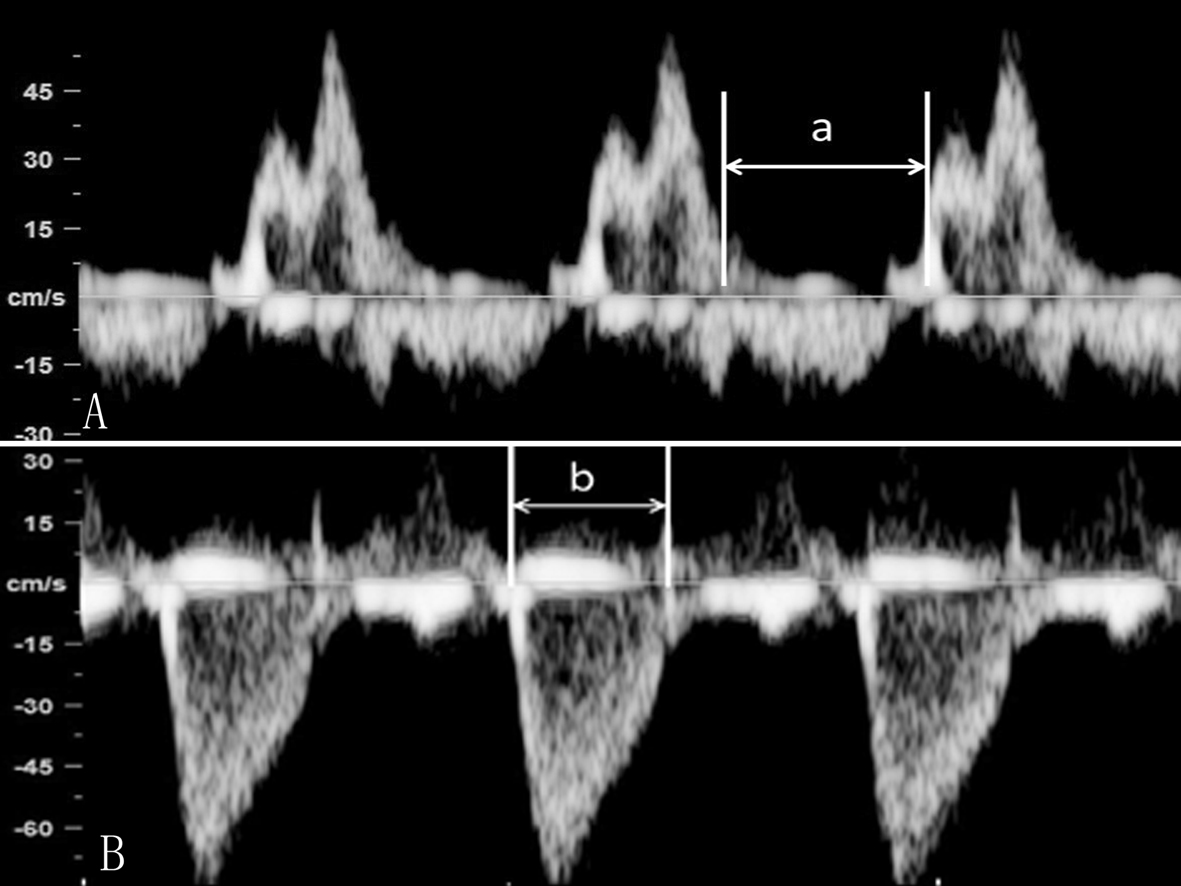

CDFI检查胎儿二尖瓣口(MVO)显示为稍细的红色血流,三尖瓣口(TVO)的红色血流较MVO稍粗;TVO的血流速度较MVO快。在瓣口远端取样,可以获得MVO和TVO的血流频谱,舒张期显示E峰和A峰。E峰由心室舒张的快速充盈血流形成,A峰由缓慢充盈期心房收缩、血流加速而形成,双峰特点在MVO显示的更为明显(图1)。瓣口血流速度随着孕龄的增加而增加,但38孕周后血流速度有所下降。

图1 MVO(A)和TVO(B)流速曲线,E峰<A峰

胎儿心室充盈的最大血流速度出现在心房射血期,由此导致MVO和TVO显示E峰小于A峰,提示心房收缩在胎儿心室充盈中起了重要作用;随着孕周增加E/A比例增大,说明心室舒张能力逐渐增加。出生24h后E/A即可升至1.17。TVO流速>MVO流速,显示胎儿循环为右心室(RV)优势;这种右室优势在早孕期即开始,直到在孕晚期才逐渐转为左室优势。

(1)MPI计算:①频谱多普勒检查心脏时,显示胎儿心脏五腔观,取样门放置在二尖瓣前叶远端和LV流出道结合部位,可以同时获得MVO血流和LV流出道血流,测量二尖瓣血流频谱前一心动周期A峰结束到下一心动周期E峰开始的时间间期,记为A,测量LV流出道血流时间为B,MPI = (A - B) / B;也有作者采取分别在MVO远端和AO瓣口获取血流频谱计算MPI的方法。②胎儿心脏TDI检查时测量显示Ea峰起点至Aa结束的时间(a)以及Sa持续时间(b),通过(a-b)/b获得MPI(图8、图9)。